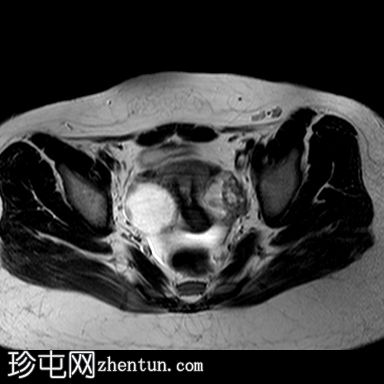

矢状位

T2加权像

阴道明显扩张,T1加权像呈中高信号,T2加权像呈高信号,耻骨联合下方可见一小局灶性隆起。

子宫大小正常,分区解剖结构正常。宫颈MRI表现正常。